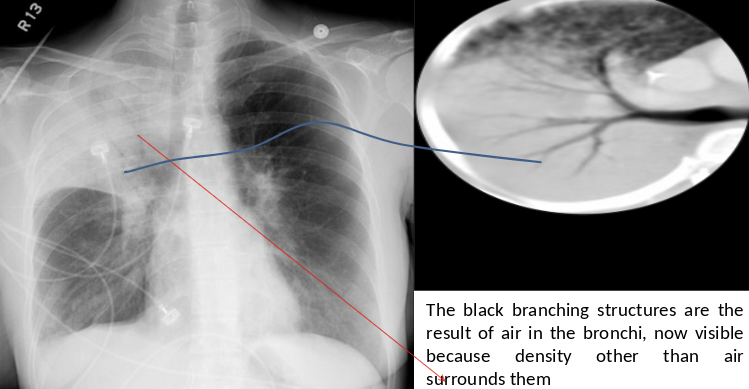

Air Bronchogram

Normally, it is not possible to identify air in bronchi within normally aerated lung, because the walls of the normal bronchi are too thin and air-filled bronchi are surrounded by air in the alveoli. However, if the alveoli are filled with fluid, the air in the bronchi contrasts with the fluid in the adjacent lung.

CT chest (axial plane; lung window) of a patient with a history of bacterial pneumonia

Opacification of much of the right lower lobe parenchyma is the result of air space consolidation. Pulmonary vessels are obscured and patent airways

(air bronchograms, white dashed line) are seen.